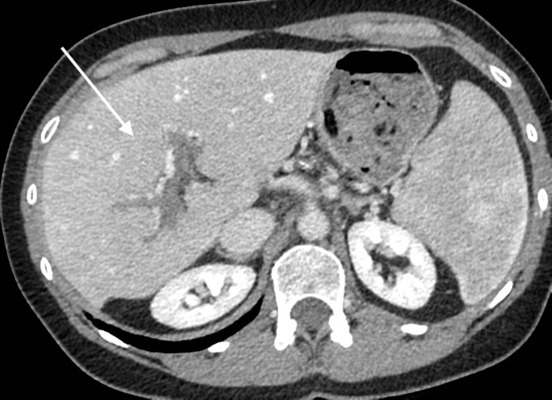

Rehaussement au temps artériel

Le foie est perfusé par la ou les artères hépatiques et la veine porte, celle-ci étant responsable d’environ trois quarts des apports sanguins. Les deux systèmes vasculaires se rejoignent pour perfuser le réseau sinusoïdal du foie. Il a été démontré qu’une baisse de la perfusion portale entraîne une augmentation compensatoire de la perfusion artérielle hépatique. Cet effet, parfois appelé «  effet tampon  », se traduit directement en imagerie par un hyper-rehaussement à la phase artérielle dans les territoires souffrant d’une baisse du débit sanguin portal.8 C’est un signe clé pour évoquer une maladie vasculaire du foie. L’hyper-rehaussement présente des limites nettes, respectant les territoires vasculaires (fig. 1). En cas de chute de la perfusion porte dans tout le foie, ce rehaussement est présent dans les régions sous-capsulaires. Il s’homogénéise aux temps veineux. La mise en évidence de ce signe doit faire rechercher toute cause de baisse de la perfusion portale (thrombose, compression, maladie microvasculaire, etc.).